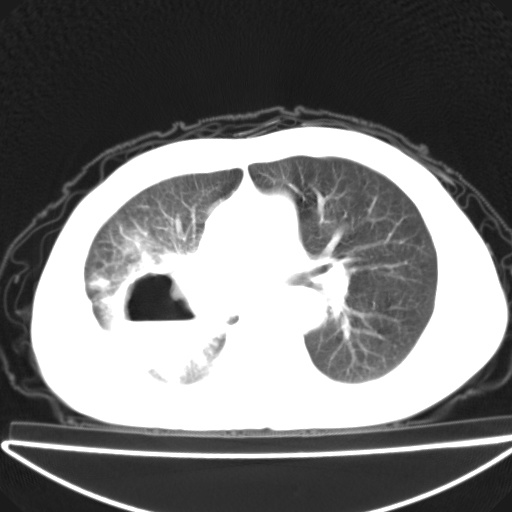

以下是引用jsgdoctor在2008-11-6 22:12:00的发言:[br]右主支气管壁明显增厚,管腔狭窄.考虑为右侧中央型肺癌伴阻塞性炎症\\肺脓肿.

以下是引用zjzjr在2008-11-6 20:25:00的发言:[br]中心型肺ca,合并阻塞性肺炎

以下是引用zsl6918在2008-11-6 19:43:00的发言:[br]右侧中心性肺癌(鳞癌)